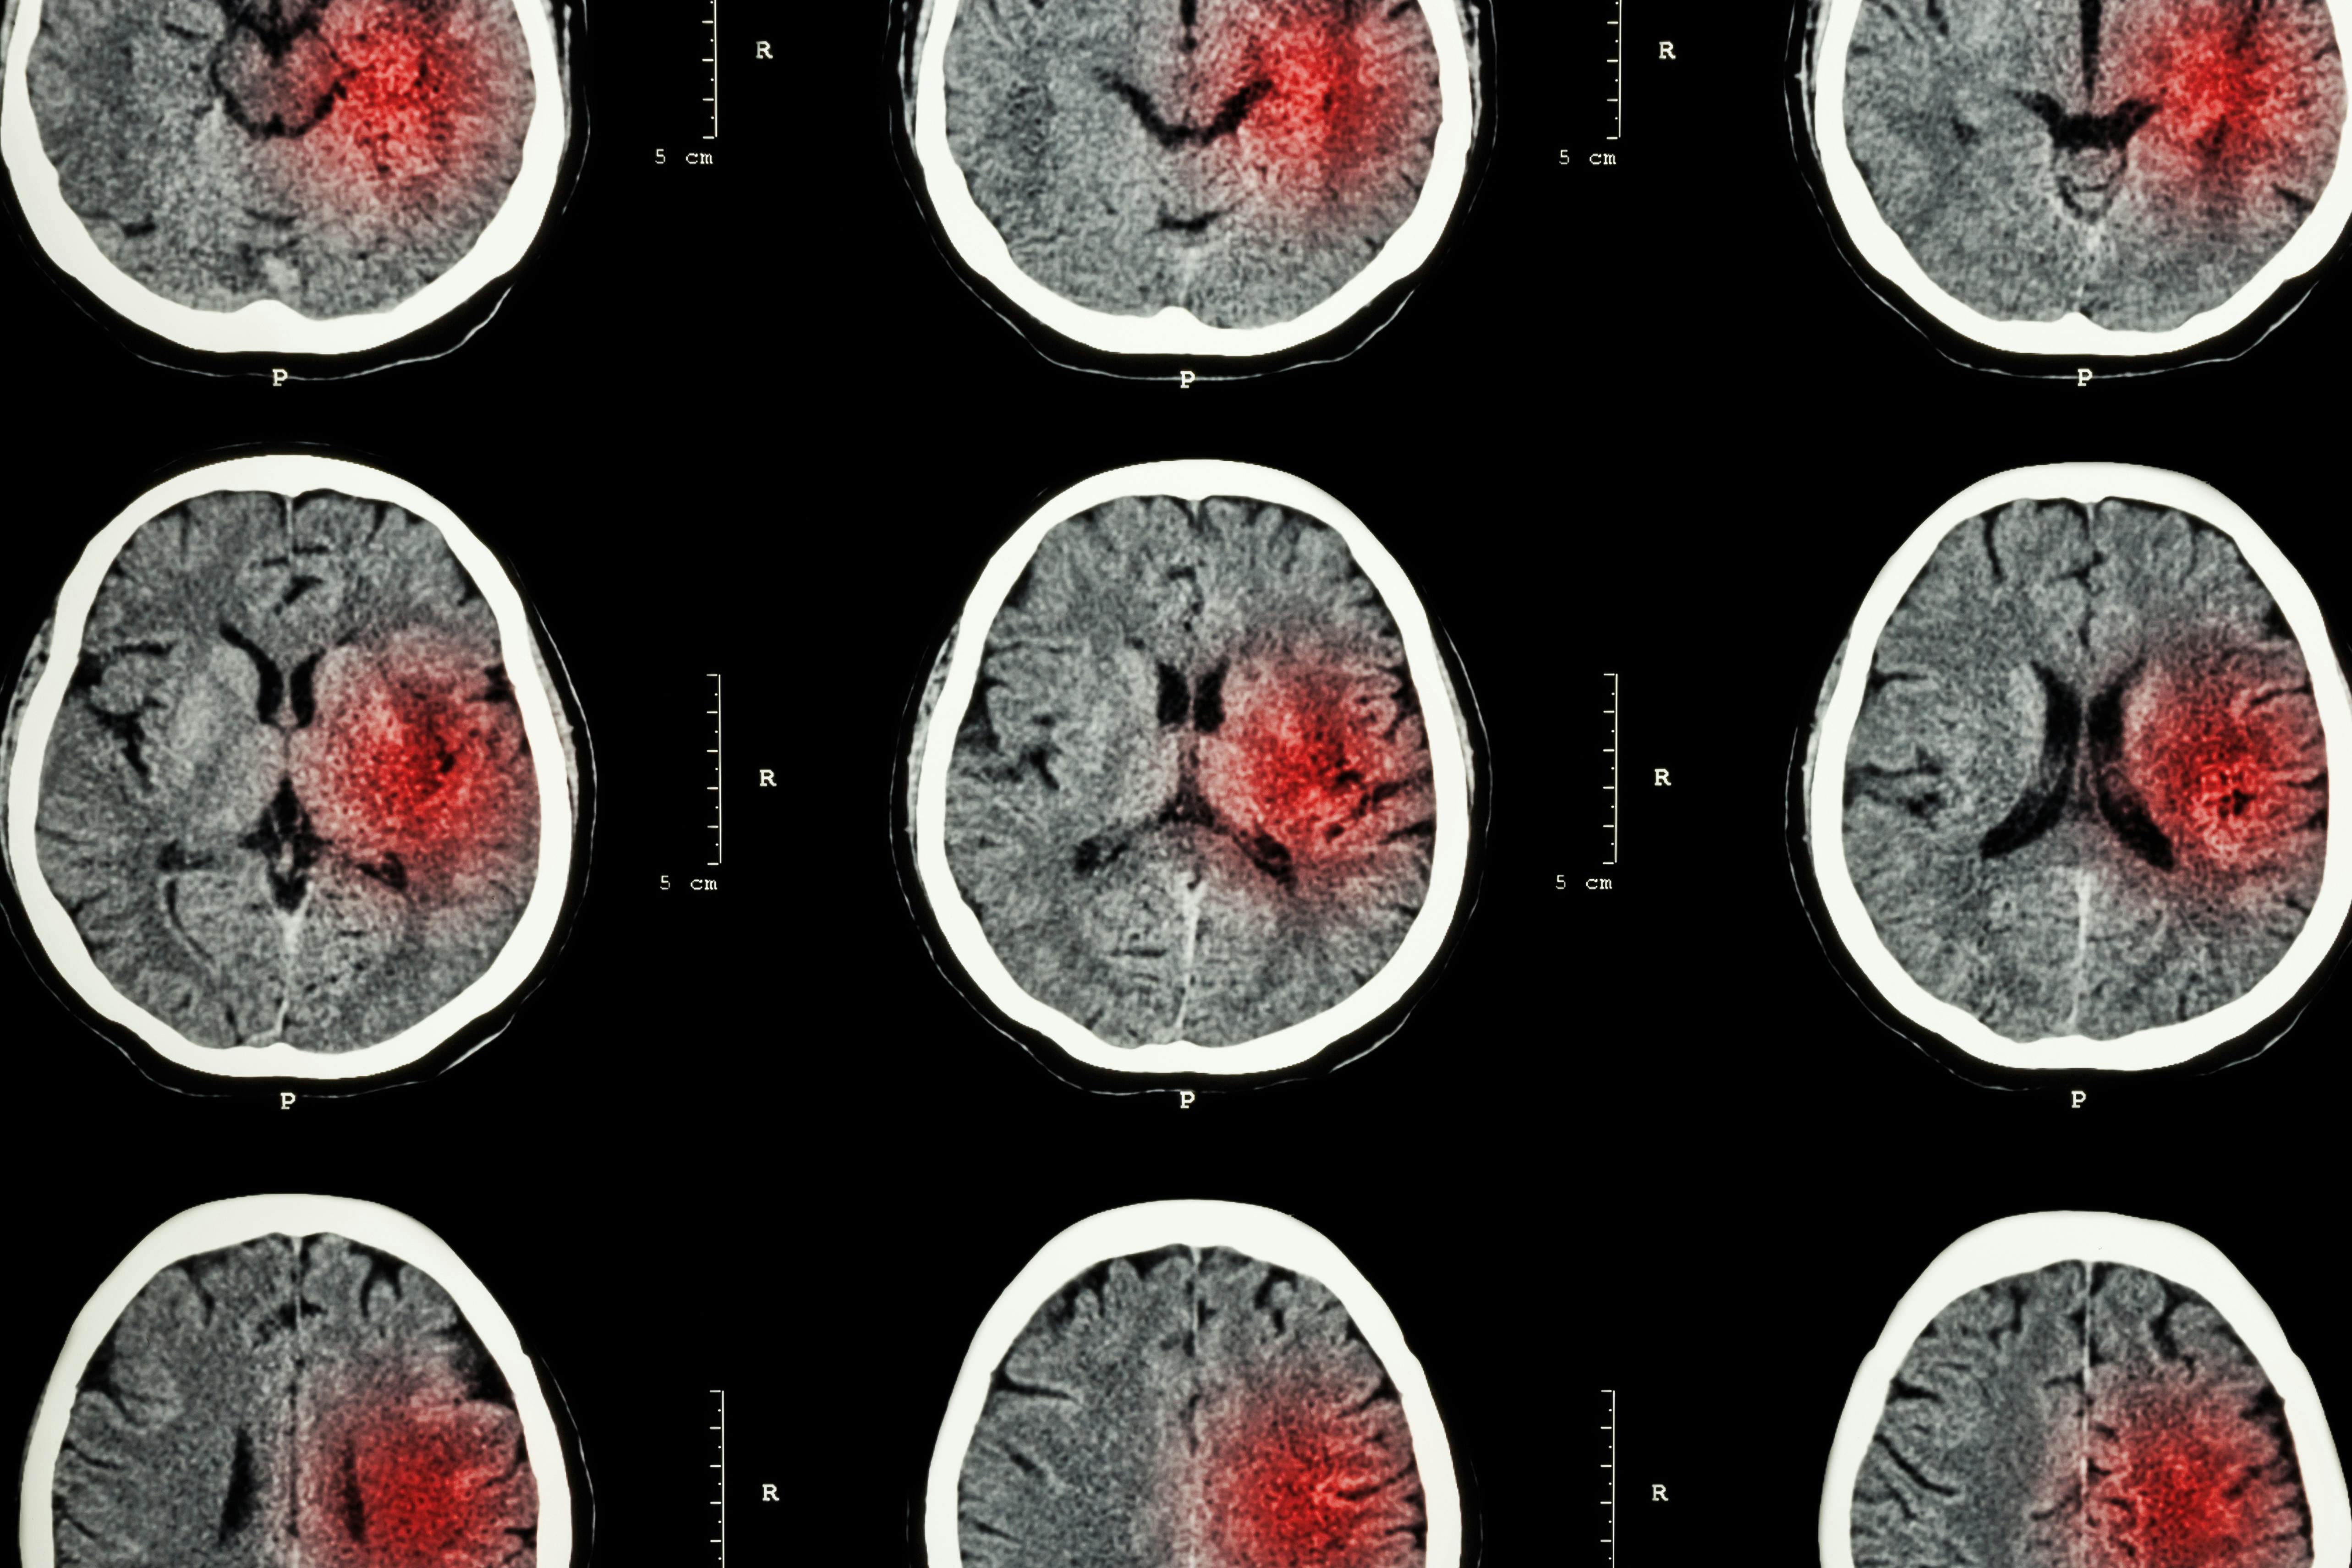

These cells are called NKG2D+CD8+ T cells and researchers say their aggressive response is responsible for neurological damage suffered from infections beyond just Zika, like COVID-19 and even septic shock.

The aggressive response is the result of the body producing large amounts of inflammatory proteins called cytokines, which in moderation help to coordinate the body’s response in battling an infection or injury by telling immune cells where to go and what to do when they arrive.

"If our body’s immune cells overreact and over produce inflammatory cytokines, this condition will lead to non-specific activation of our immune cells which in turn leads to collateral damage. This can have severe consequences if it happens in the brain,” Ashkar says.